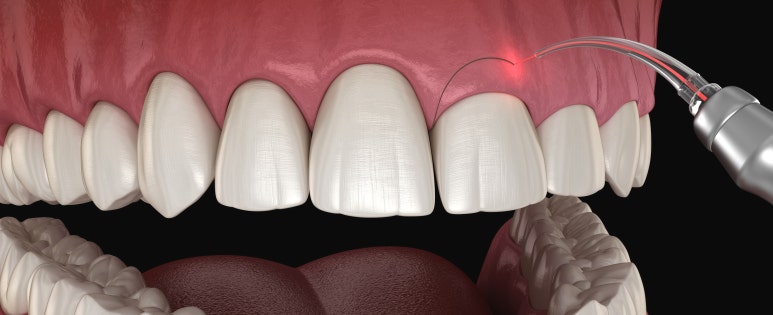

상기 환자분 전체적으로 잇몸라인이 평평하고, 치아가 네모나게 보이는 것이 고민이 되어 잇몸성형을 받기 위해 내원해 주셨습니다.

24세 여성

(전) 2022-06-11, (후) 2022-06-25

레이저를 이용해서 전체적으로 잇몸라인을 동그랗게 다듬어드리고 높이도 양측 균일하게 맞춰드렸습니다.

전후 사진 비교해 보시면 이전보다 치아 형태가 더 예쁘고 시원한 느낌이 드는 것을 확인하실 수 있는데요.

실제 웃거나 말씀하실 때 잇몸이 많이 보이는 것도 고민이셨는데, 이 부분도 개선되어 환자분도 많이 흡족해하셨습니다. ^^

레이저를 이용한 잇몸성형 시술시간은 국소마취 시간을 포함해서 약 30분 정도이며,

레이저로 섬세하게 시술해 드리고 있어 통증과 출혈을 최소화하고 있지만, 개인에 따라 당일 약간의 출혈과 통증, 붓기 등이 있을 수 있고요.

회복되기까지 약 2~3일간은 붉은 기운과 쓰라인 느낌이 있을 수 있습니다.